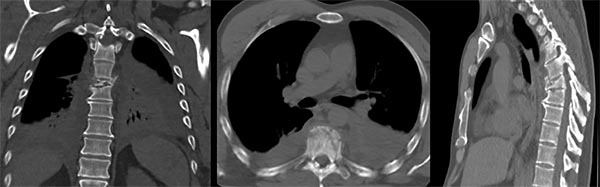

Figura 4:

Caso 8. Hombre de 52 años, accidente vehicular de alta energía cinética. Fractura cerrada de antebrazo, síndrome de distrés respiratorio, hemotórax bilateral, hematocrito en descenso. Se diagnostico una fractura A4 de T8 con mínimo compromiso del canal espinal, posición en cifosis y hemotórax bilateral a predominio izquierdo.